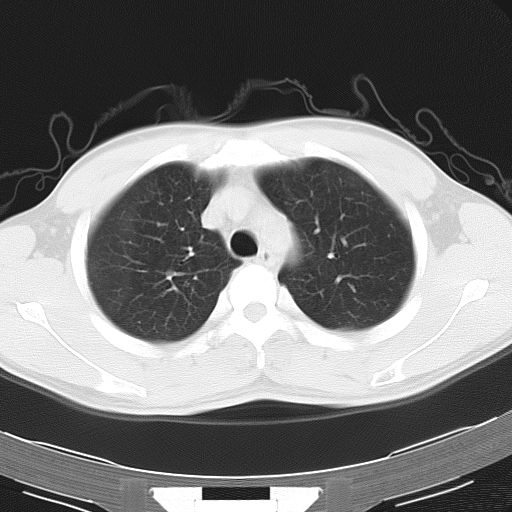

男,34岁,咳嗽2~3个月,无咳血,病初有发热。

两上肺磨玻璃样改变,均位于肺外周,考虑1、肺泡蛋白沉着症?2、肺泡炎?请询问有无养鸟史 3、脱屑性间质性肺炎?建议进一步检查、复查随访

两上肺的ggo,靠近胸膜,不是以节段分布,青年男性,个人意见为吸入性的真菌感染可能为大------------呼吸内科医生

两肺上叶近胸膜磨玻璃样阴影,考虑1、炎性病变。 。2、过敏性炎症?

病灶特点:

分布在肺野的外带,病灶边缘清楚,病灶以磨玻璃影为主夹杂少许纤维状高密度影

支持zhangzhongshou主任,考虑蛋白沉着症可能性大

再仔细阅读该病人的ct片,我们不难发现,病例所表现的正是外围型的肺泡蛋白沉积症表现,即:为多发性条片状、斑片状及斑块状高密度影,弥散、对称或不对称分布于两肺或一侧肺外围部位。病变区与正常肺组织及脏层胸膜面分界清晰,呈地图样改变。